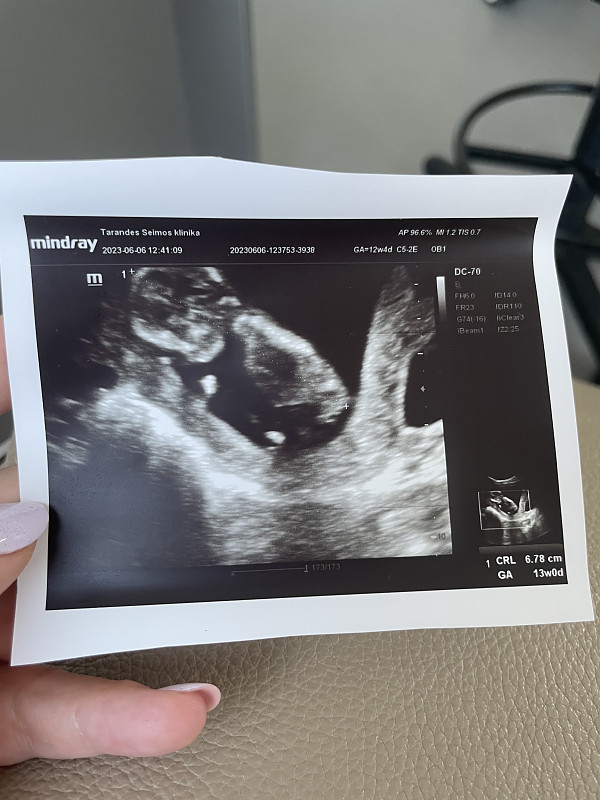

Ramzio vaisiaus lyties nustatymo teorija

Pagal Ramzio teoriją kūdikio lytį galima nustatyti labai anksti, 6-8 nėštumo savaitę iš pradėjusios formuotis placentos vietos. Skaityti visą straipsnį